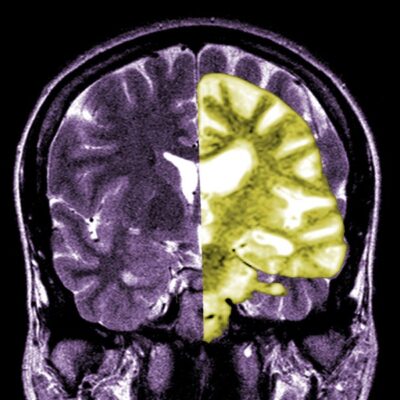

A composite MRI image showing a healthy brain (left) and one with advanced Alzheimer’s disease (right).Credit: Jessica Wilson/Medical Body Scans/Science